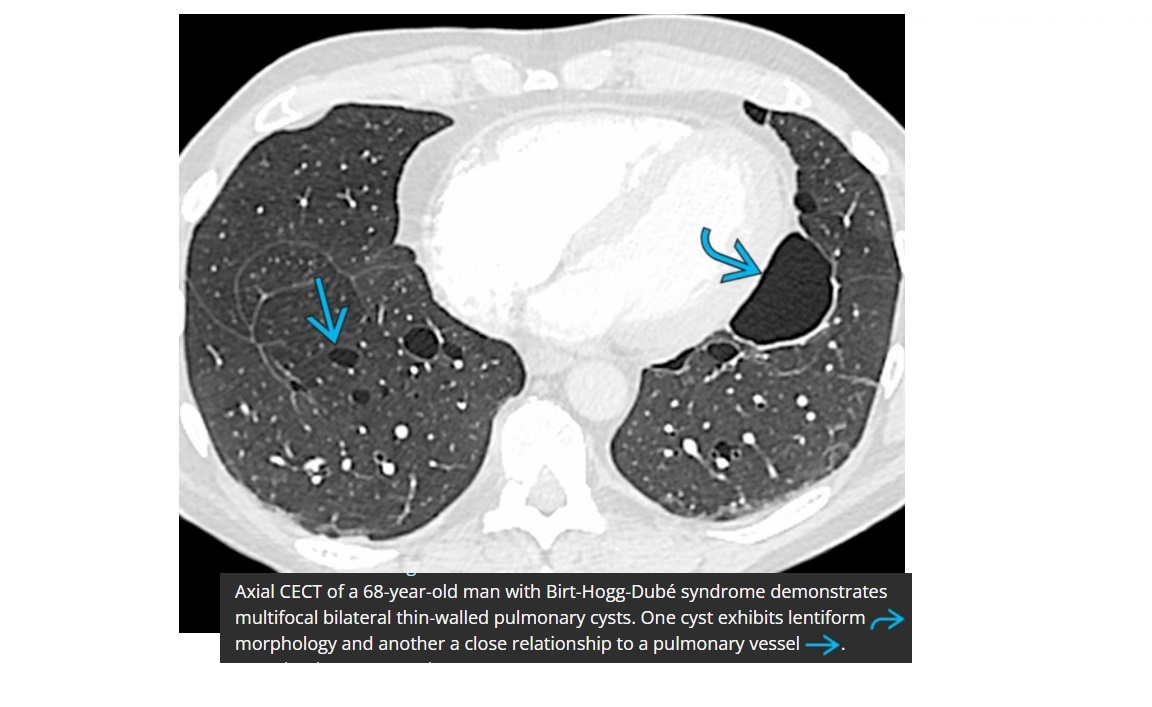

Birt-hogg-dube

Bilateral basilar predominant lentiform cysts abutting pleura, septa, and pulmonary vessels

Liver and skin lesions

Bilateral Renal oncocytomas

+ **chromophobe RCC